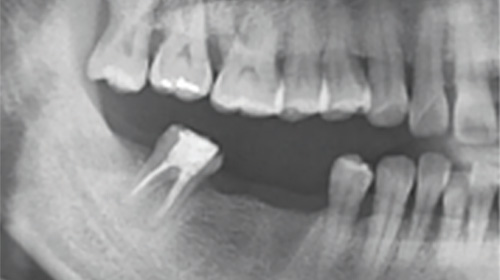

歯の欠損の状態(失われた歯の本数および部位)や顎の骨の状態(骨の厚さや量、密度、神経や上顎洞との関係など)により、

インプラントに適応できないこともあります。